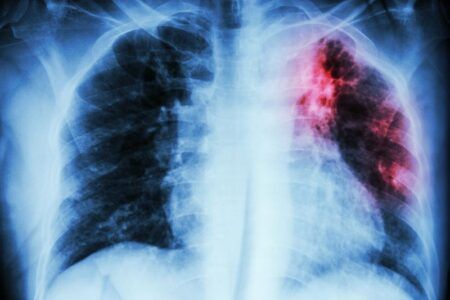

La pandemia de COVID-19 ha anulado años de progreso mundial en la lucha contra la tuberculosis, una enfermedad causada por un germen que suele afectar a los pulmones.

Tuberculosis